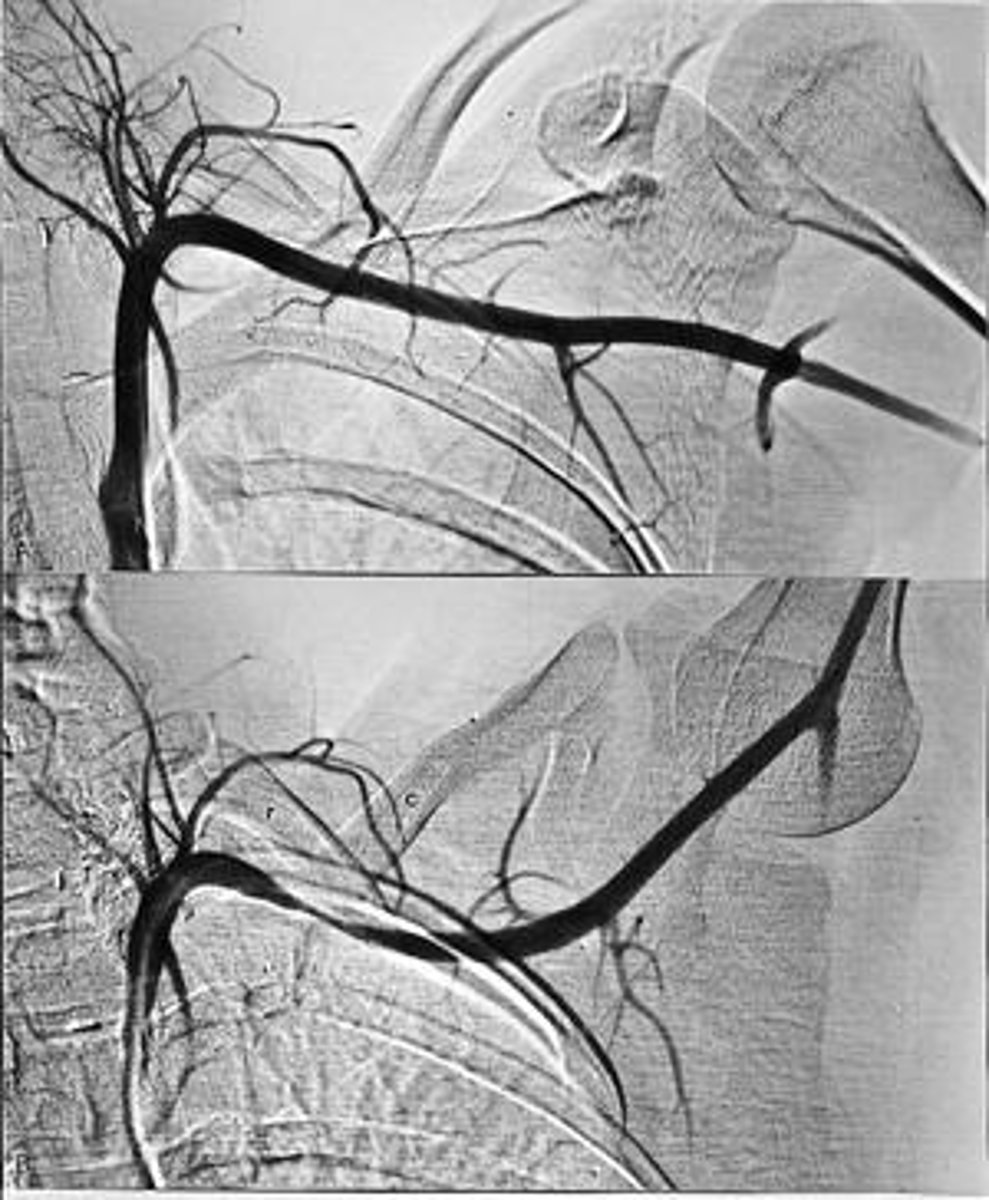

Ateriography

radiography of arteries after injection of radiopaque material into the bloodstream

Arteriogram

Aortography

radiography of the aorta

Aortagram

record produced from a aortography